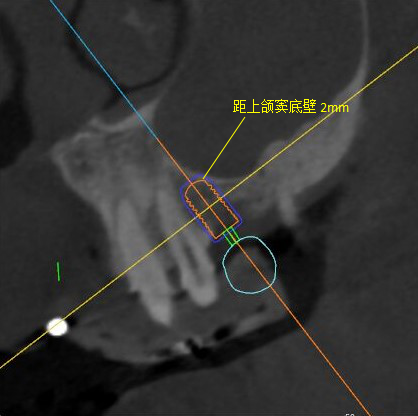

矢狀面視圖

根據(jù)患者CT顯示,使用種植導(dǎo)航軟件設(shè)術(shù)前手術(shù)方案??紤]到患者拒絕手術(shù)摘除上頜竇囊腫等因素,此次手術(shù)選用了Straumann骨水平4.10*8.0mm的植體,植體末端位點(diǎn)設(shè)計(jì)距上頜竇底壁2mm處的同時(shí)兼顧種植方向和修復(fù)間隙,來(lái)達(dá)到理想的效果。

導(dǎo)航下精細(xì)分配修復(fù)間隙,精細(xì)規(guī)劃植入方向,避開(kāi)上頜竇底,精確植入